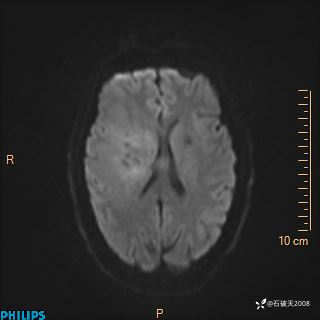

2020.11.14MR

DWI